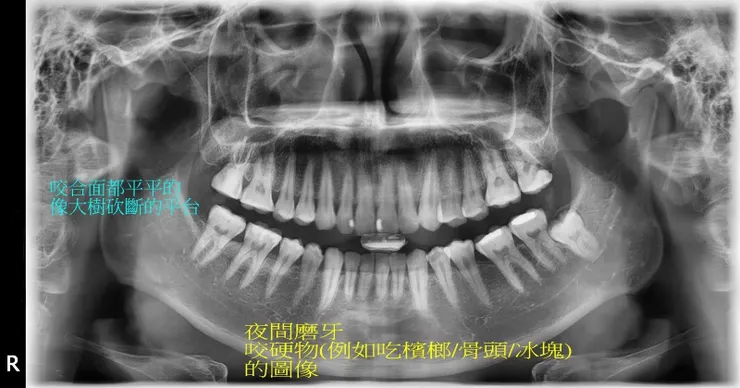

夜間磨牙通常是心理壓力大引起,顯現在口腔,其危害甚大

常有人好奇磨牙會怎麼磨掉牙齒?剛好有個適當的例子做說明。